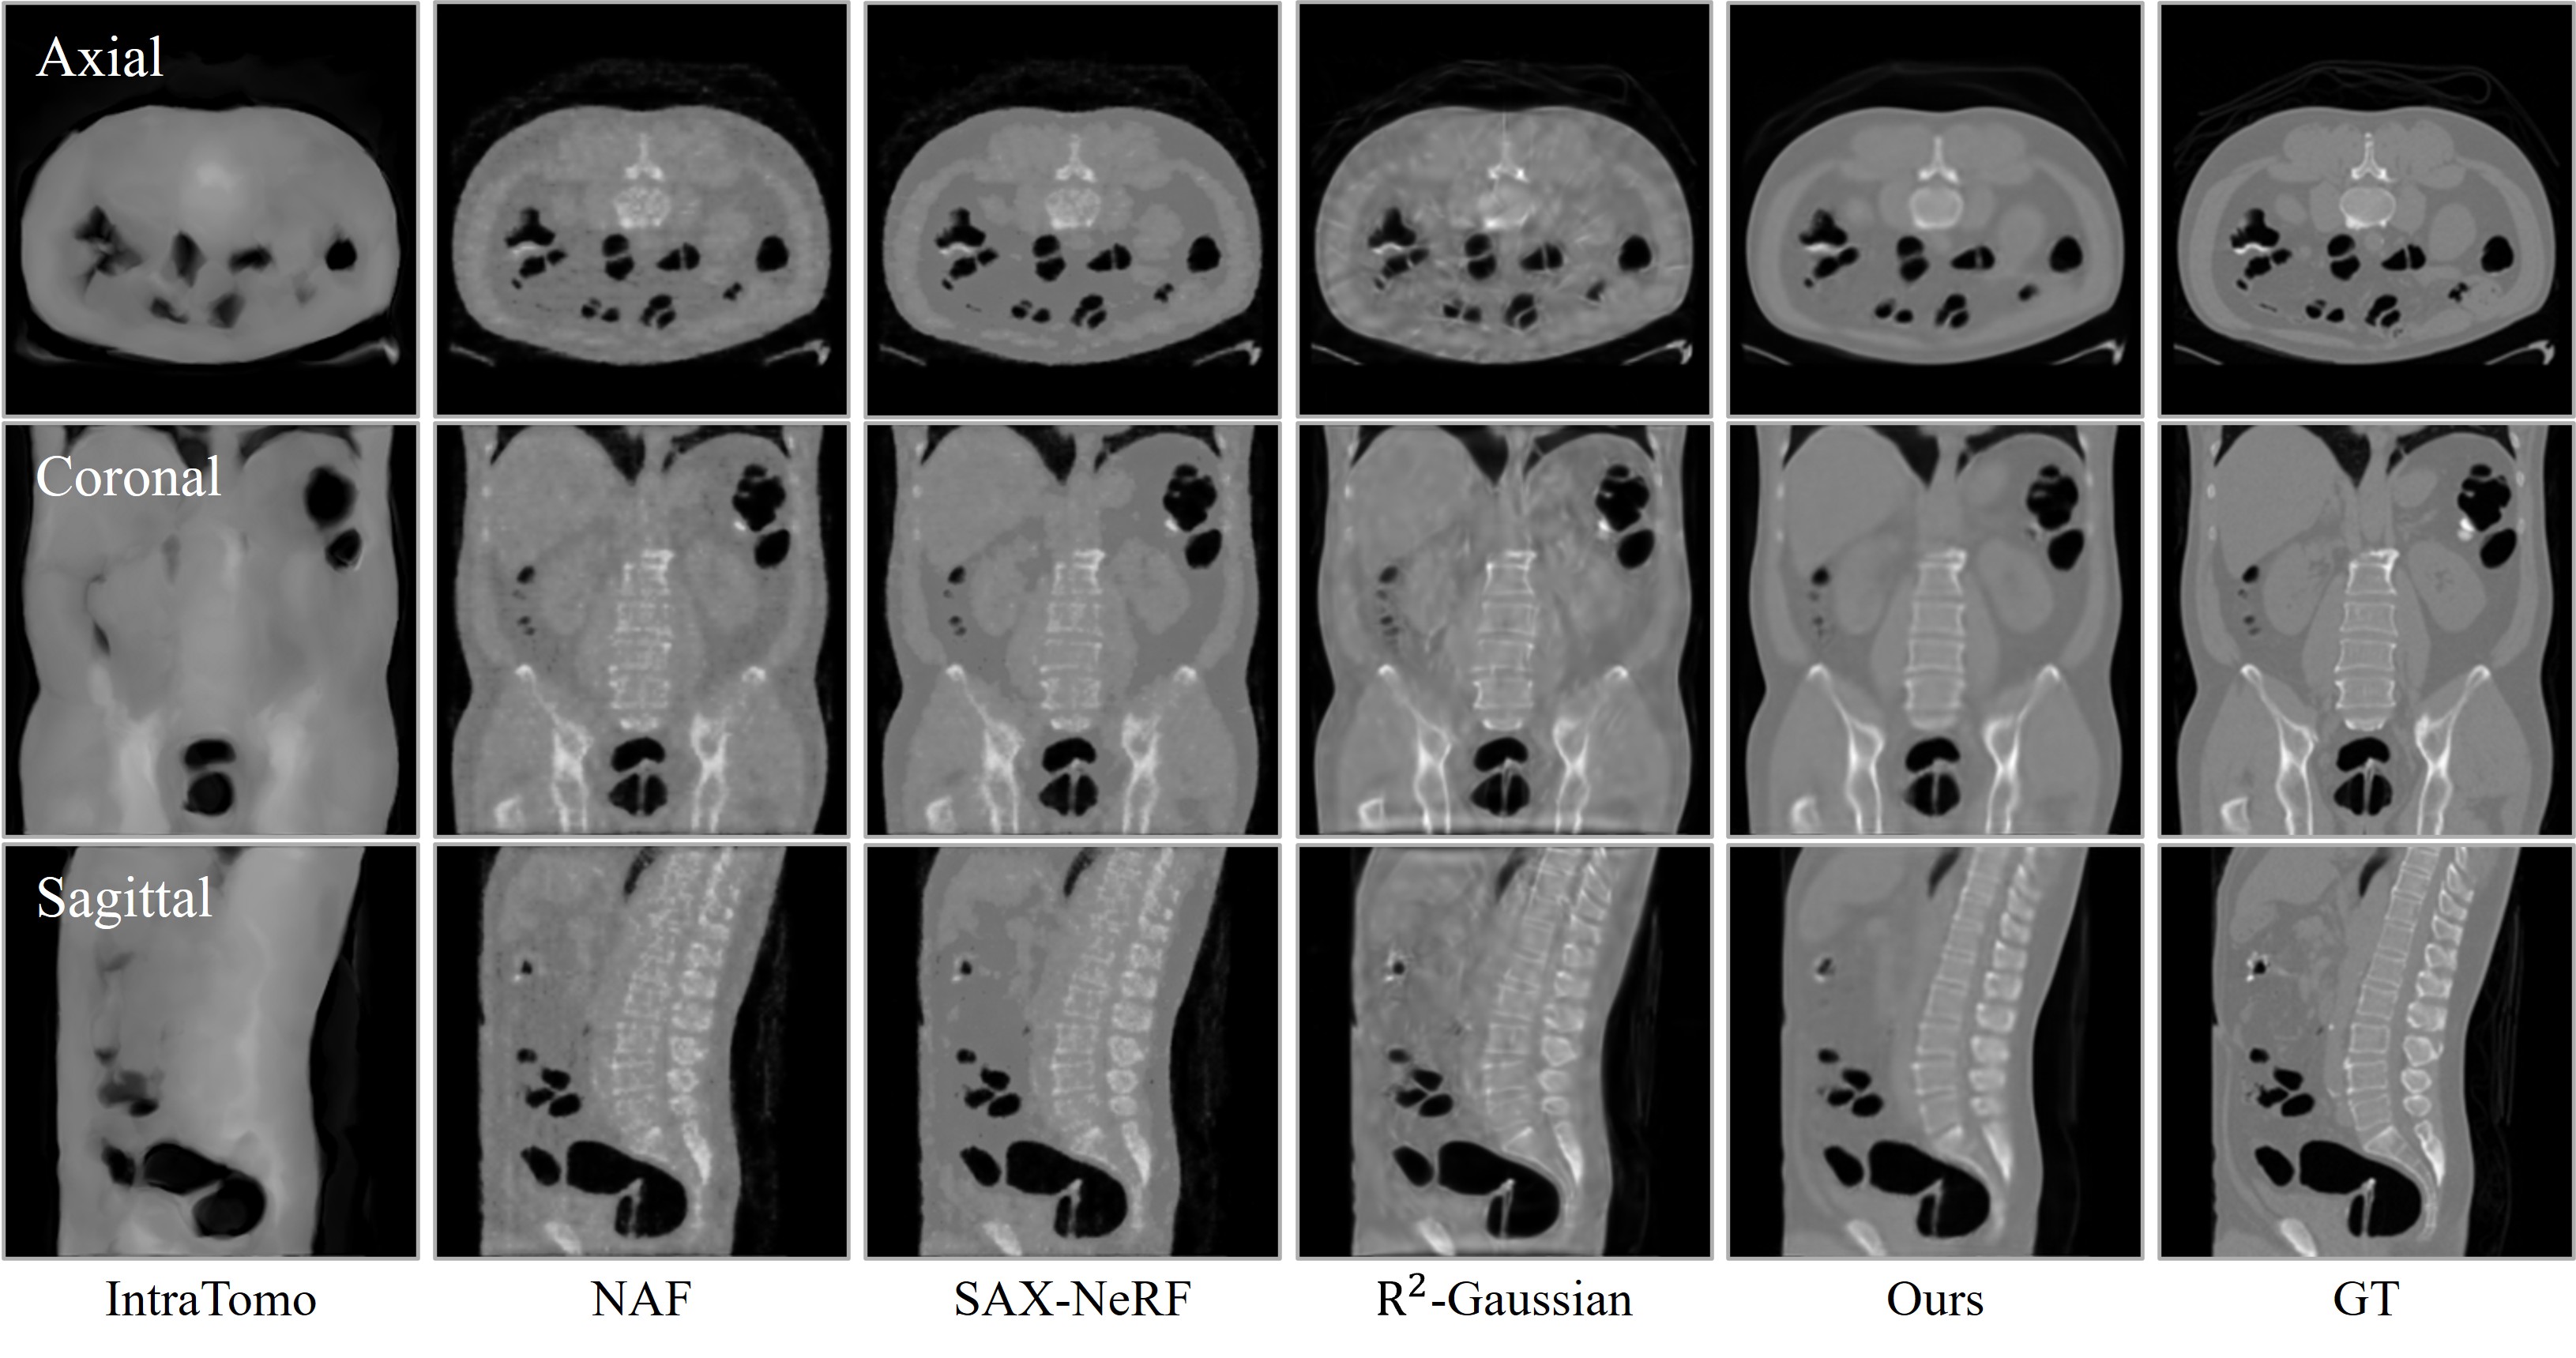

Visual comparison of CT reconstruction across different views. ILV achieves significantly cleaner structural details and consistency under both 10-view and 24-view sparse settings compared to existing methods.